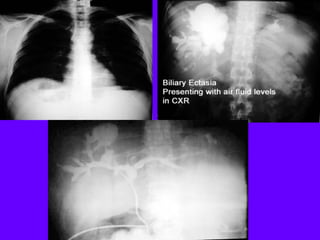

Chest radiology part 3